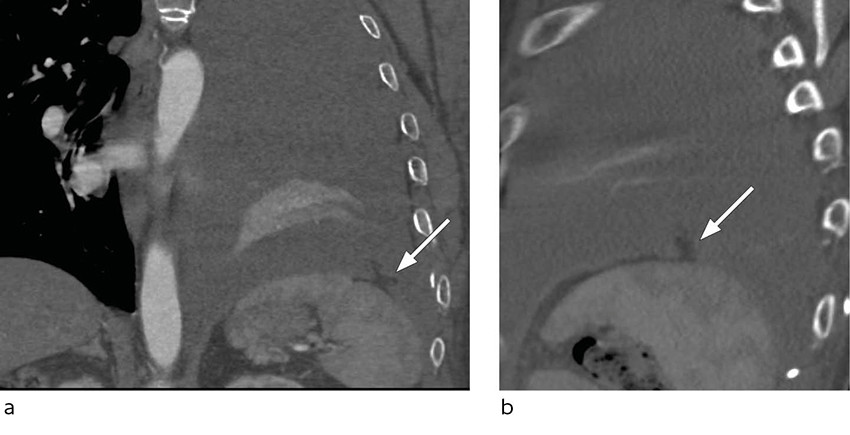

After two days of treatment with intrapleural alteplase, the patient became unwell and developed left-sided chest pain. The symptoms subsided when he lay down, following which his blood pressure was 130/80 mmHg, heart rate 70 bpm and the peripheral oxygen concentration 97 %. A total of 400 mL of bloody fluid in the drainage bag was recorded. A few hours later, the patient again became unwell and hypotensive. The blood pressure was now 55/30 mmHg and the haemoglobin concentration had dropped from 9.4 to 8.2 g/dL during the course of the day. The patient received intravenous fluids and a unit of erythrocytes, and his condition stabilised. He was awake and pale, and his blood pressure was 100/60 mmHg. A chest X-ray revealed an increasing pleural effusion (Figure 1). The subsequent chest CT confirmed massive haemothorax with mediastinal deviation and a fatty structure in relation to the diaphragm (Figure 2). Shortly after the scan was taken, the patient's heart rate had increased to 118 bpm. His blood pressure remained steady at 110/72 mmHg. A thoracostomy was performed urgently with a 28 French chest tube, which immediately drained 1 litre of blood.

Figure 2 Chest CT with intravenous contrast, in coronal (a) and sagittal (b) plane, with a small defect in the left side of the diaphragm with a small fatty structure protruding up into the pleural cavity, representing the bleeding omentum.

Video-assisted thoracic surgery the same day revealed bleeding omentum protruding through an antero-lateral laceration in the diaphragm. The protruding omentum was excised and the laceration sutured thoracoscopically. A laparoscopy was performed, but no additional lacerations were found. The recovery period was without further complication and the patient was discharged after seven days.